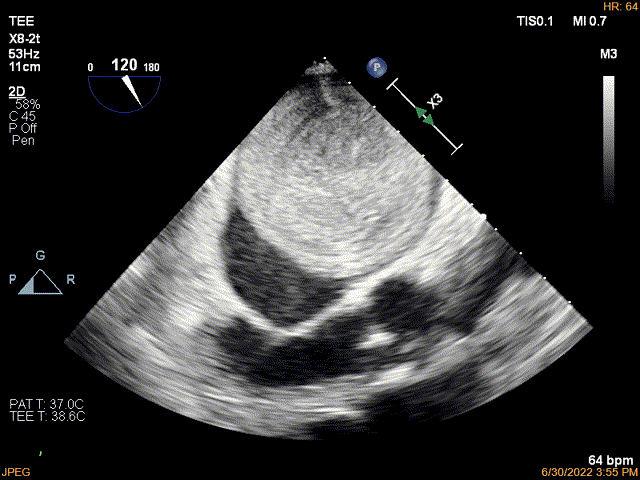

一名69岁女性患者,有脑梗死和持续性非瓣膜性房颤病史,因言语不清、大小便失禁就诊于急诊科。该患者于2018年发生过脑梗死和房颤,之后间断服用达比加群。达比加群自行停药一个月后,再次发生脑梗死。心电图显示为房颤。经胸和经食道超声心动图均显示,患者左心房内存在一个67×60mm的巨大肿物,占据了左心房的大部分空间,并能观察到肿物可阻塞二尖瓣口(图1A和视频)。

A 经食道超声检查发现左心房内有一个58×55mm的可移动球形肿物。